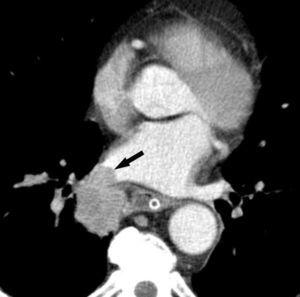

Fig. 2.--T4. (A) Corte axial de tomografía computarizada (TC) torácica con contraste. Tumor hiliar derecho que infiltra la arteria pulmonar derecha, la vena cava superior y engloba al bronquio intermediario. (B) Reconstrucción coronal oblicua, longitudinal al eje de la arteria pulmonar derecha, que muestra cómo engloba el tumor a la rama del truncus superior (flecha blanca) e inferior (flecha negra).